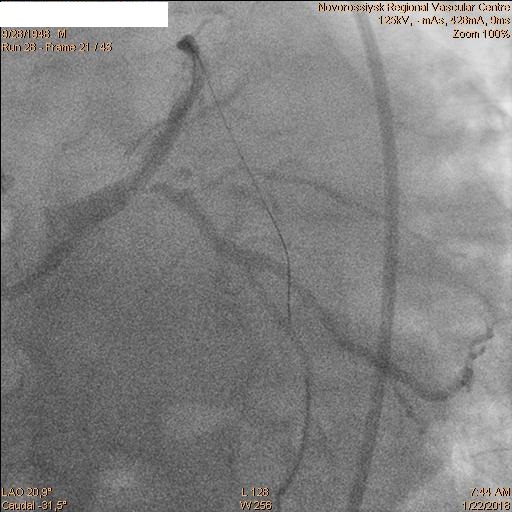

В 06.00 пациент в экстренном порядке подан в рентгеноперационную. Пациенту выполнена коронарография, по данным которой выявлены стеноз ствола ЛКА 60% с переходом на устья ПНА и ОА, окклюзия ПНА от устья и стеноз устья ОА 60%.

После которой было принято решение о выполнении бифуркационного стентирования ствола ЛКА.

Последовательно заведены коронарные проводники в дистальные сегменты ПНА и ОА. Первым этапом была выполнена реканализация, баллонная ангиопластика ПНА баллоном 2.5х20 мм и стентирование ствола ЛКА с переходом на проксимальный сегмент ПНА стентом 4.0х28 мм.